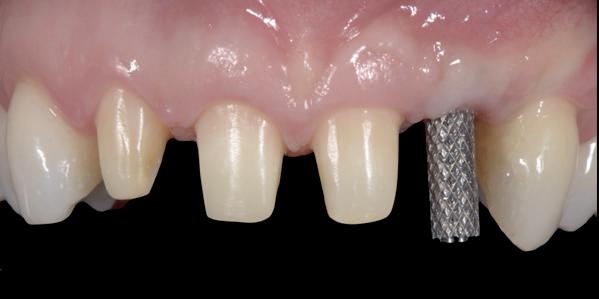

De flap en graft worden met poly-propelene 6.0 hechtingen gefixeerd. De tijdelijke reconstructie wordt herplaatst (foto 17-20).

Na 4-6 weken kan het aangebrachte healing abutment worden vervangen door een tijdelijk abutment. Deze wordt aan de kunststof reconstructie verbonden om zo de gingiva ter plaatse van de 22 te vormen. Zo lijkt het of er geen implantaat maar nog steeds een wortel aanwezig is, wat het esthetisch eindresultaat ten goede zal komen (foto 21-23). Vanaf 4-6 maanden ziet het weefsel er gezond uit. Nu kan met de uiteindelijke restauratiefase worden gestart (foto 24 en 25).